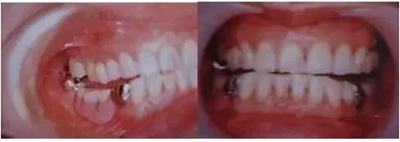

1、咬合高度不協(xié)調(diào)

A. 高度減少

作為因正常后方磨牙部咬合支撐喪失引發(fā)的下頜過閉口咬合,磨牙處部分性發(fā)生的情況稱為后牙咬合崩塌(posterior bite collapse)。

磨牙部咬合支撐的喪失是逐漸由殘存的牙齒的牙齒移動和不恰當?shù)难例X修復(fù)體所引發(fā)的。左右磨牙以及前磨牙完全喪失的情況下,閉口時沿著上頜前牙舌面傾斜的下頜的前方牙齒接觸的方向,這時髁狀突非旋轉(zhuǎn)地工作并被施加后方閉口力,導(dǎo)致髁狀突的遠中和上方變位,會引發(fā)下頜功能異常的肌肉癥狀。

制作全口義齒的患者情況下,咬合高度設(shè)置低一些會引發(fā)閉口肌的收縮,有時會引發(fā)筋膜疼痛。

B. 高度增加

這是咬合高度過度增加以至于能夠封閉自由空間(freeway space)的情況,作為制作的修復(fù)體的結(jié)果,這會引發(fā)肌肉過度伸長、肌肉過度緊張、肌肉疲勞和疼痛。